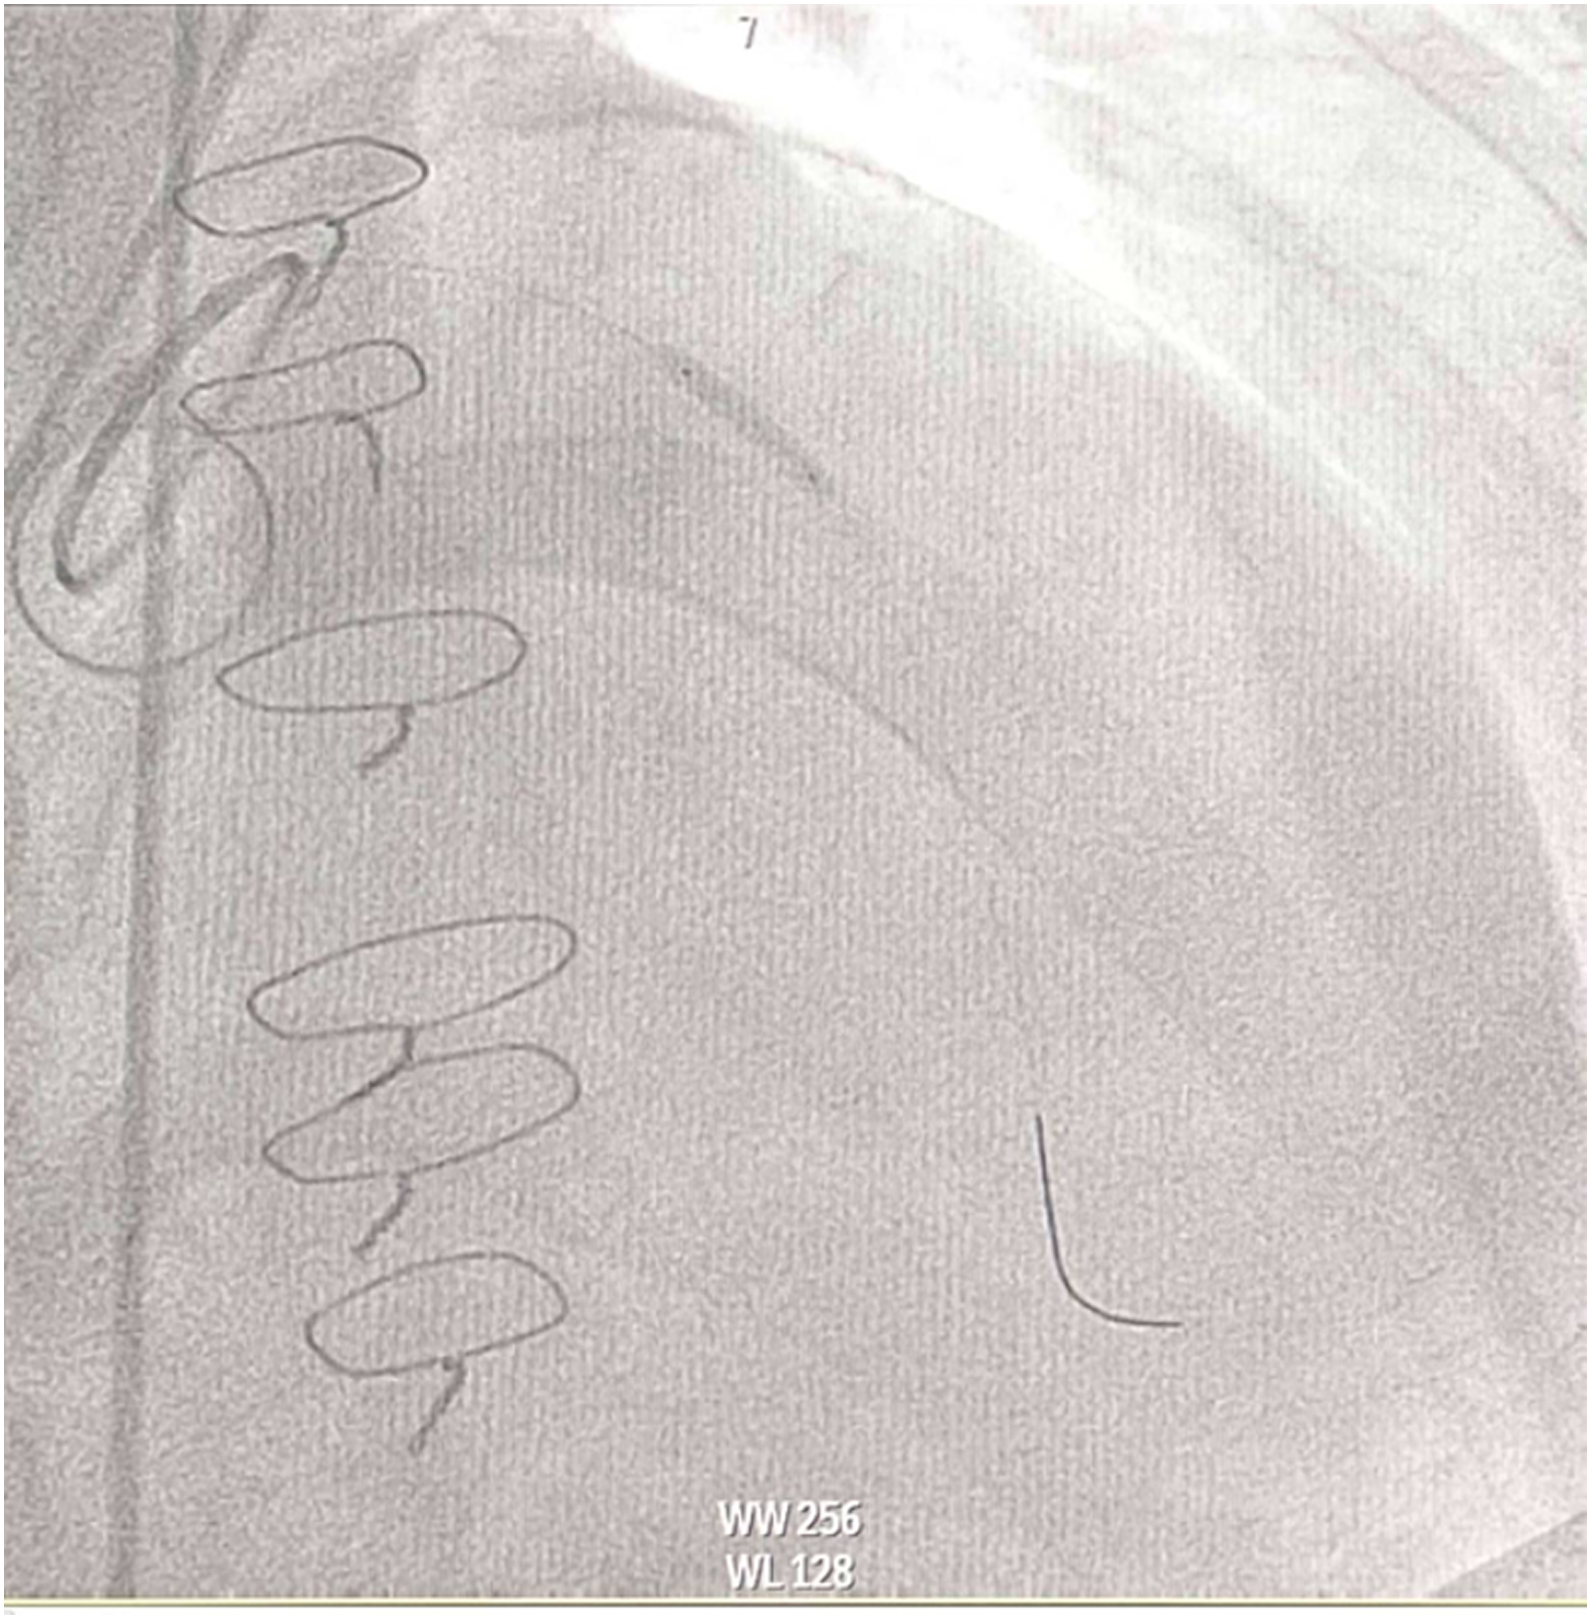

Inserted Sion wire and thrombuster to LAD revealed multiple red clots.SC balloon 2.0 x 15 mm, then 2.5 x 15 mm, was inflated at mLAD up to 12 atm. IVUS insertion to LAD revealed vessels¡¯ size LM 5-5.5 mm, pLAD 4-4.5 mm, mLAD 3-3.5 mm with intraluminal thrombus, dLAD 2.75-3 mm. Multiple inflations were done at mLAD with SC balloon 2.5 x 15 mm. After multiple SC balloon inflations, the CAG revealed slow flow phenomenon. Then, the operator performed thrombus aspiration, multiple SC balloon 2.0 x 15 mm inflation and gave IC integrillin 3.4 ml. The final angiogram was acceptable result. The anticoagulant was given after CAG. Chest pain was subsided and hemodynamic parameters remained stable. EKG recorded after angiography showed resolution of ST elevation at V1-3. Later, the patient was discharged with warfarin. The Aortomitral intervalvular fibrosa repair surgery was planned due to embolic complication.